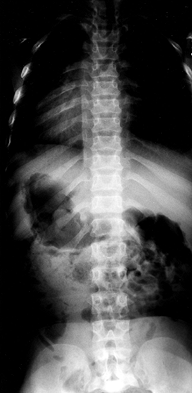

as a “champagne glass” appearance. The radiographic hallmark of the

achondroplastic spine is progressive narrowing of the transverse

interpedicular distance as one measures from cephalad to caudad in the

lumbar spine (Fig. 180.3). The pedicles are thickened, and there may be posterior scalloping of the vertebral bodies.

Figure 180.3. Progressive interpedicular narrowing in the lumbar spine of a 5-year-old girl with achondroplasia.